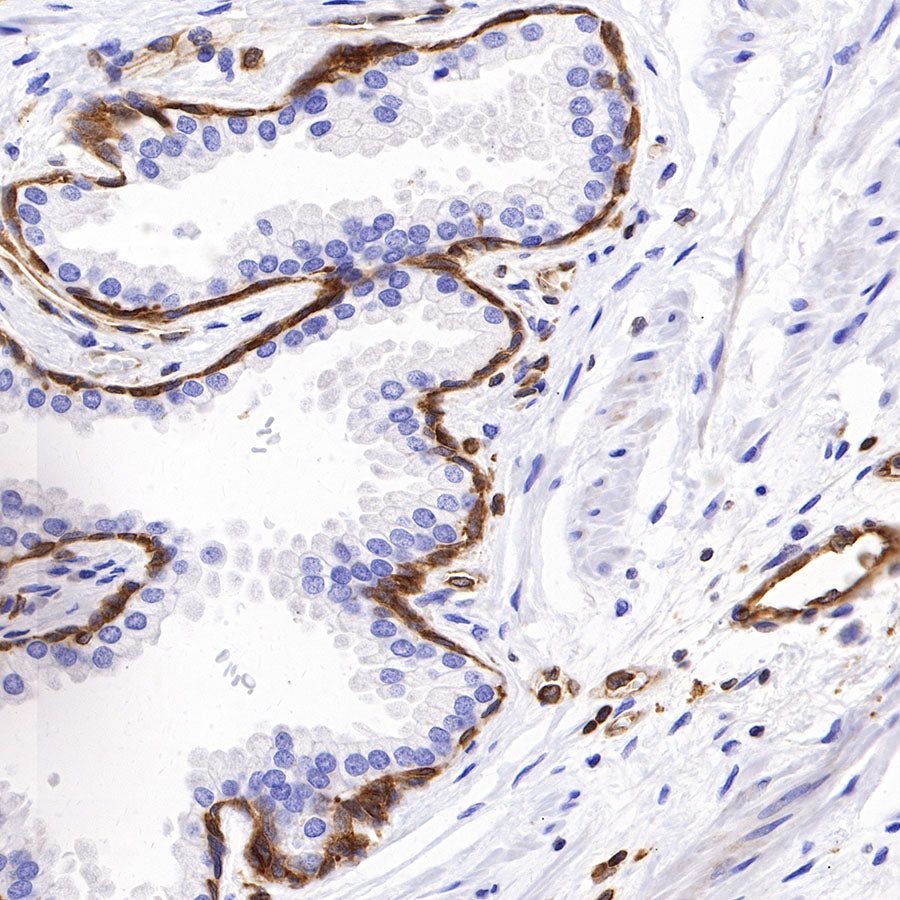

Picture

Picture

Immunohistochemistry